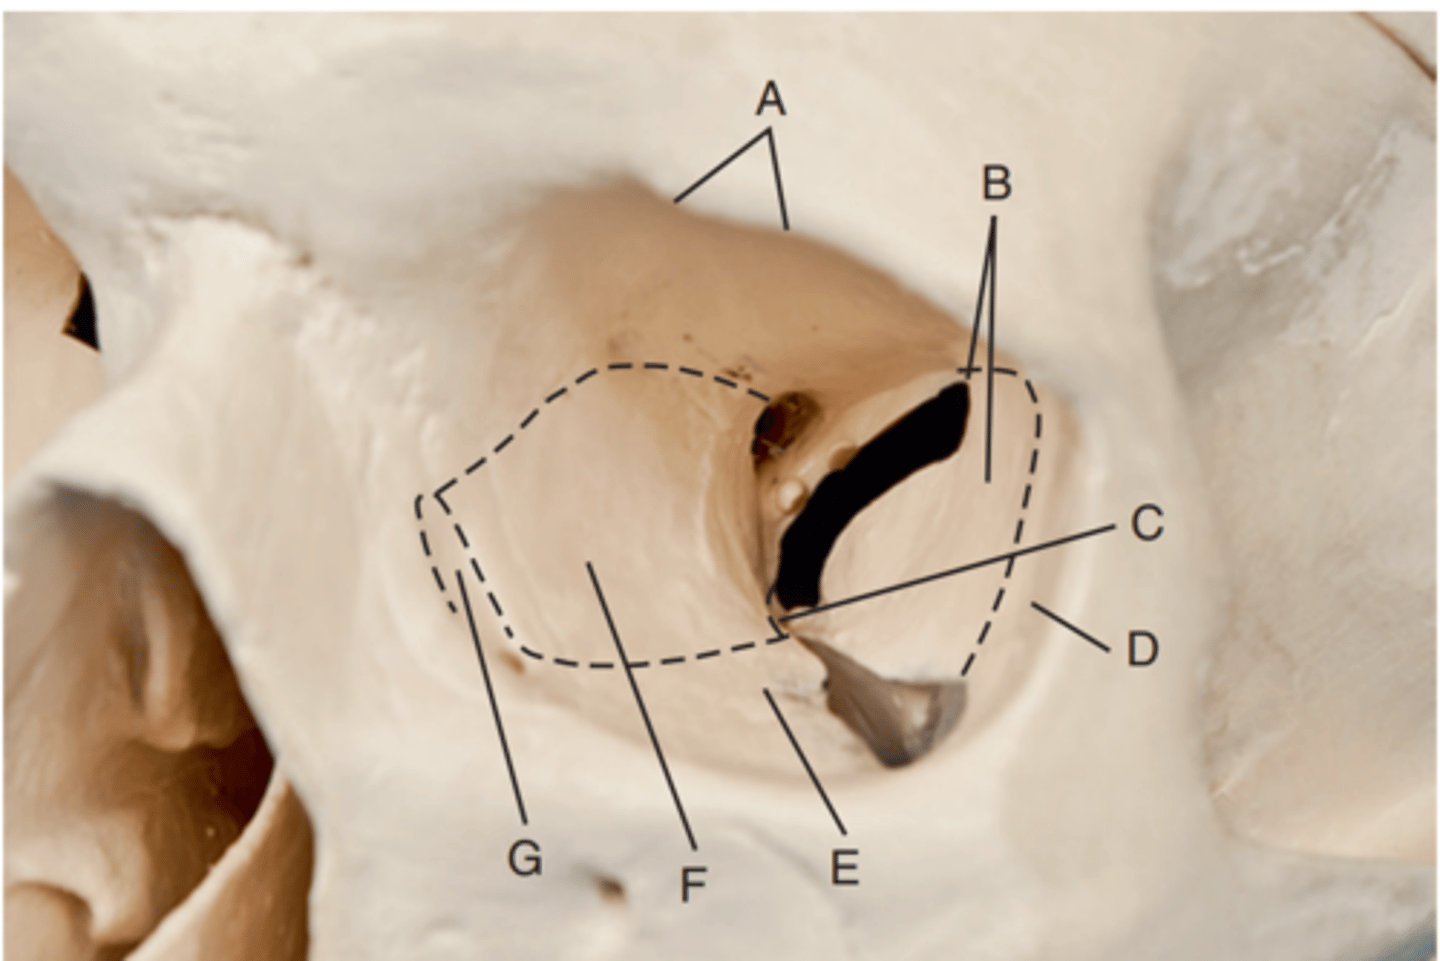

Optic foramen

Label A

Sphenoid strut

Label B

Superior orbital fissure

Label C

Inferior orbital fissure

Label D

Orbital plate of frontal bone

Label A

Sphenoid bone

Label B

Optic foramen and canal

Label C

Superior orbital fissure

Label D

Infraorbital margin (IOM)

Label E

Sphenoid strut

Label F

Lateral orbital margin

Label G

Supraorbital margin

Label H